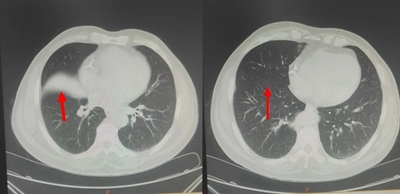

治疗期间,鲍主任根据丁大爷症状改善情况及时调整方剂配伍。服药一周后,丁大爷咳嗽、胸闷症状明显减轻;两周后,呼吸顺畅度显著提升,可正常活动;复查胸部CT显示,双肺炎症较前基本吸收,受压的右肺中叶肺组织已完全复张。